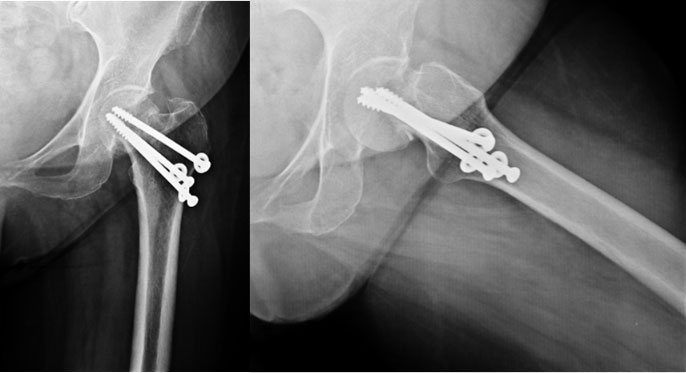

In her sleep one day she suddenly felt a sudden sharp pain in the hip joint, afterwards she was ok, so she continued to walk on the leg. She came back to us after a few days of limping and not being able to walk as earlier. The x-rays at that time showed this picture – where the screws had cut out of the ball (femoral head) and were even pinching on the socket. This was the cause of her pain, limp & shortening.

Post Total Hip Replacement

The xray picture after total hip replacement. The socket (acetabular cup) was fixed with bone cement whereas the femoral stem is uncemented. The length of the limb has been restored.